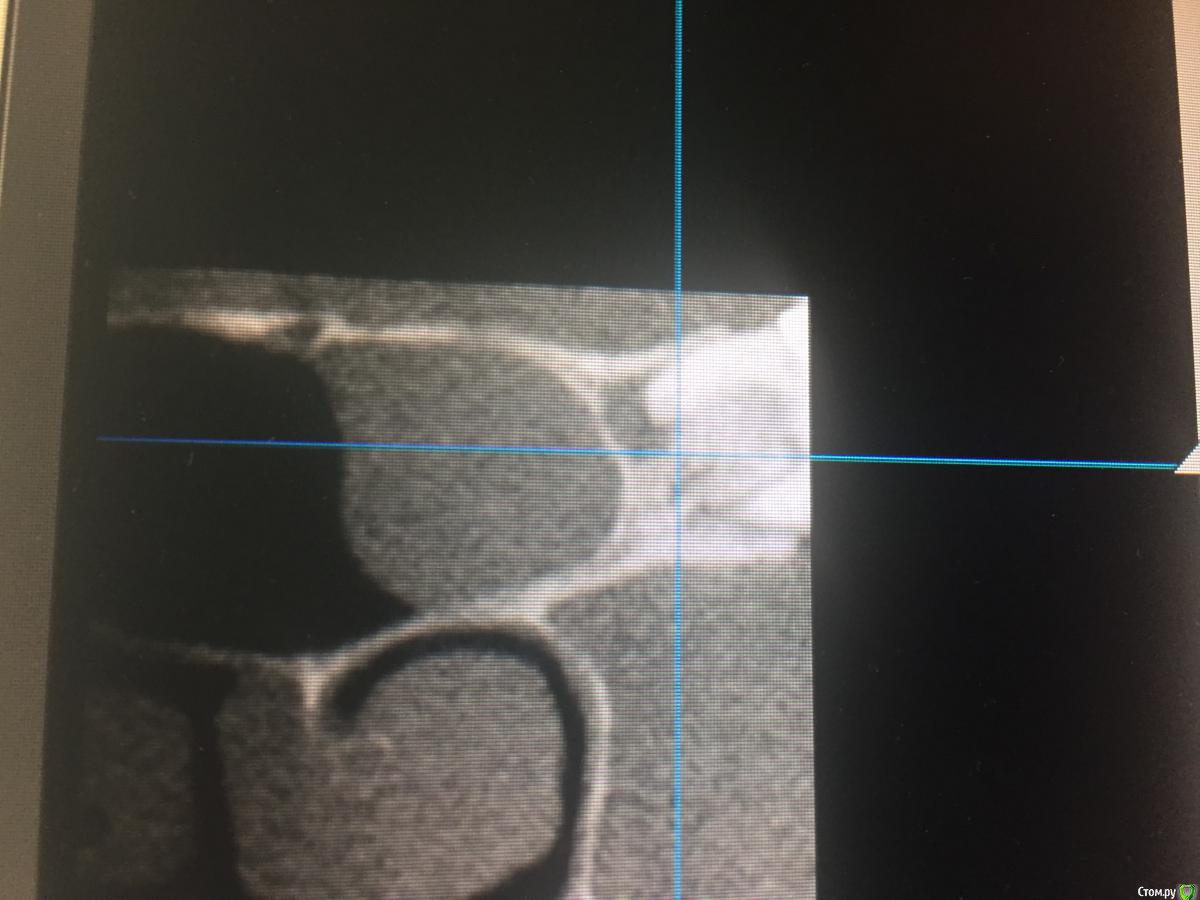

TIGER Опубликовано 26 октября, 2016 Поделиться Опубликовано 26 октября, 2016 (изменено) Доброго времени суток коллеги!Вот такая "штука " обнаружена на КТпричина тоже видна ,это 28 зуб...соустье в норме...вопрос:необходима установка имплантов и синус ,но и удаление 28 естественно...во время паботы в синусе как поступить с этим затаившимся злом?)у кого есть опыт?буду признателен ✌ Изменено 26 октября, 2016 пользователем TIGER Ссылка на комментарий

Nazim_NV86 Опубликовано 26 октября, 2016 Поделиться Опубликовано 26 октября, 2016 Добрый вечер. В передней стенке на уровне верхнего края кисты виден сосуд. Это первое. Кисту можно удалить и сделать синус лифтинг. Где то на форуме был кейс. Вы делаете два окна друг на другом. Через верхнее опорожняете и вылущиваете кисту. Через нижнее - синуслифт. Ссылка на комментарий